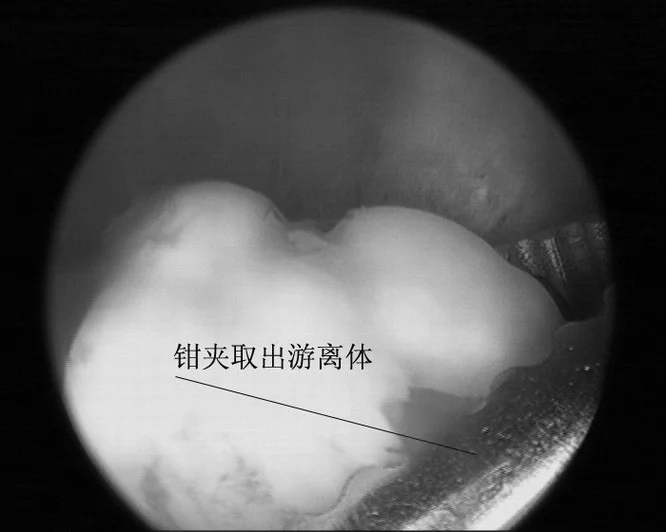

治疗主要是摘除关节内游离体,可切开关节施行,也可在关节镜下取出。对带关块律满超节面的骨软骨碎片尽可360百科能复位固定。